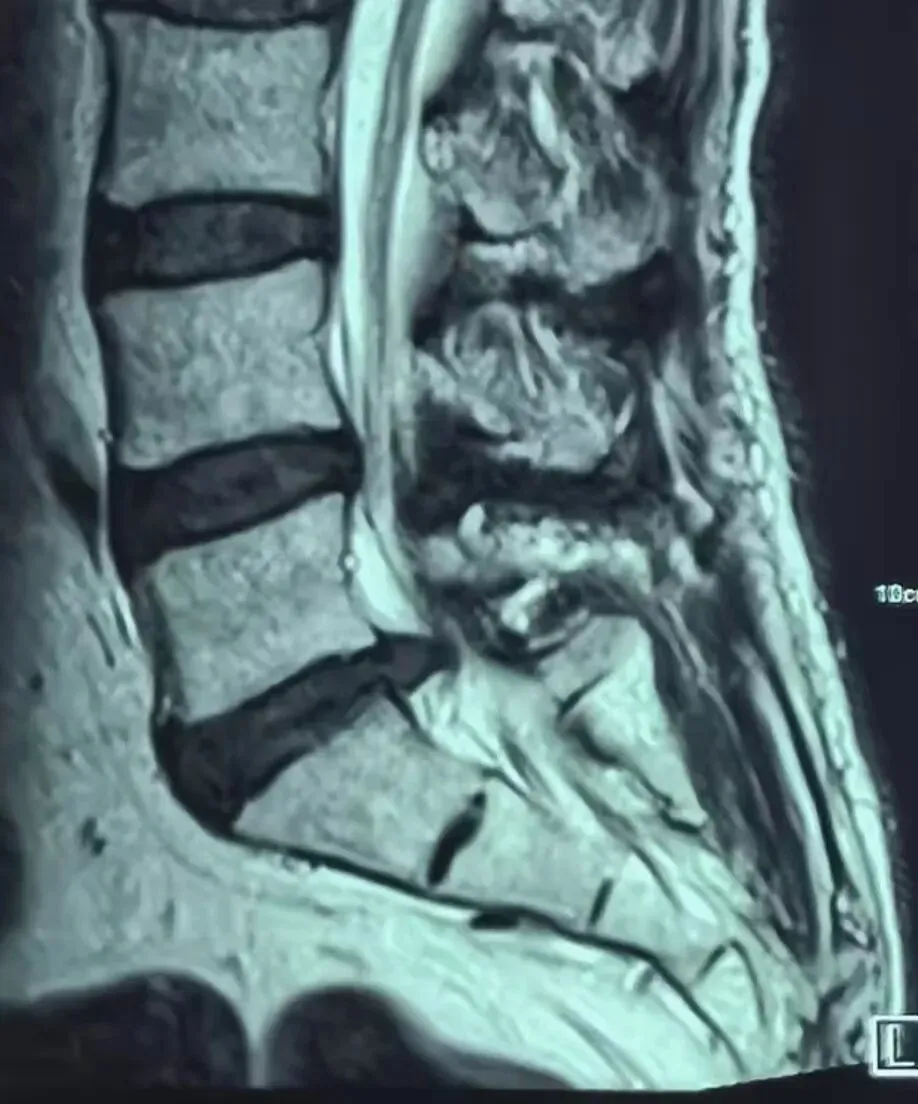

近日,我院骨科团队在外聘专家李丽教授带领下,为一位68岁腰椎间盘突出患者行经皮椎间孔镜下后路椎板减压、椎间盘髓核摘除、神经根粘连松解术。患者术后第二日便可下地行走,对骨科团队精湛医术连连点赞。

经皮全脊柱内镜后路椎板切除(减压)术、腰椎间盘突出摘除术及脊髓神经根粘连松解术属于微创脊柱核心技术,其重要性在于创伤小、对脊柱稳定结构破坏少、出血少、恢复快,可精准解除椎管、神经根压迫,避免神经缺血与功能损伤,降低术后并发症与脊柱不稳风险;有效性体现在能直接去除突出髓核、扩大椎管容积、松解瘢痕粘连,显著缓解腰腿痛、麻木、间歇性跛行等症状,神经功能恢复确切,远期疗效稳定;适应性主要针对腰椎间盘突出症、腰椎管狭窄症、神经根粘连及腰椎术后复发等病症,适用于保守治疗无效、以神经根受压为主要表现的患者,尤其适合老年及基础疾病较多、对手术耐受较差的人群。